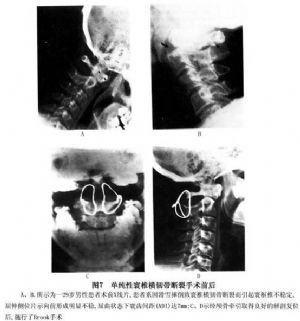

14.3.2 Brook手术

Brook手术多用于单纯性寰枢不稳者,因勿需对寰椎进行复位,因此可将钢丝穿过植骨片,并使之与枢椎靠拢(植骨块下方中央有一缺口,可骑至枢椎棘突上),收紧钢丝即达固定融合的目的,尤其适合于年幼的患者(图6,7)。其具体操作如下: